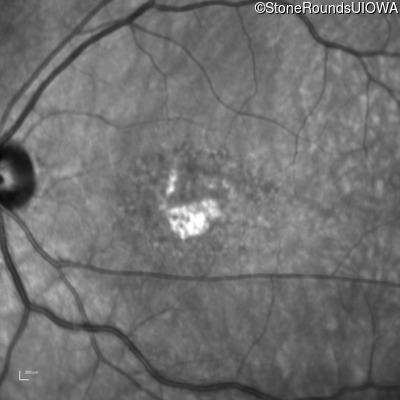

Age at visit:

54 years

OD

OS

20/160 -2

20/160 +1

AR Stargardt Disease

ABCA4

IVS40+5 G>A

Gly1961Glu GGA>GAA

AR